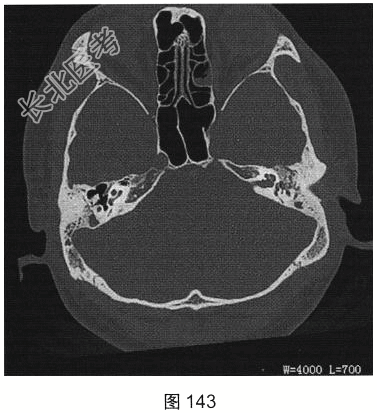

- [材料题] 患者男性,47岁,主诉间断左耳流脓10年,近期耳痛加重,既往无高血压,糖尿病及肿瘤病史。患者既往影像学检查如图143、图144所示。

- 简答题2、[提示]患者近期耳痛明显加重伴血性分泌物,再次进行了CT检查,CT影像显示患者鼓室腔内软组织影,鼓室盾板、鼓室盖及听小骨溶骨性骨质破坏,病变周围骨质毛糙。目前患者最可能的诊断是?